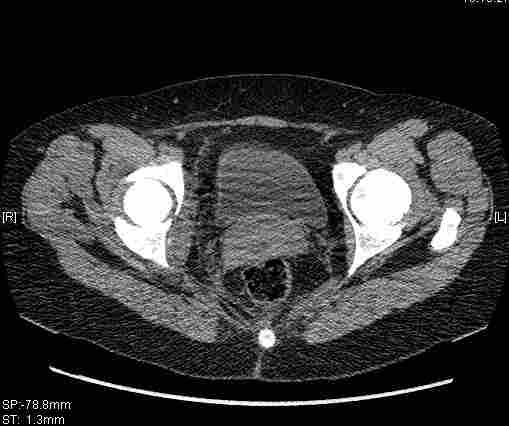

Женщина,58 лет, после ДТП 6 суток. Первично повреждение расценено как переломы ветвей лонной кости. После подтверждения повреждения вертлужной впадины,как чаще всего случается, вопрос встал о тактике. БОльшинство за консерватиное лечение.К сожалению кт у нас "во время" сломался. Прилагаю стандартные снимки вертлужки. У меня следующие вопросы к коллегам:1. Правильно ли рассценивать это повреждение как Т-образный перелом вертлужнй впадины?2. Можно ли добиться анатомической репозиции поверхности вертлужной впадины скелетным вытяжением в данном случае, если нет, что будет этому препятствовать?3. Если смещение останется таким как сейчас, через какое время появится необходимость эндопротезирования (по вашему опыту)?Спасибо.

Удалось сегодня вывести пациентку в соседнюю больницу, где есть кт. Срезы сделаны только горизонтальные.

Следом 3d